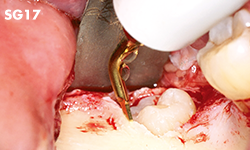

Unilateral anterior mandibular sampling

Excision of bone torus

Anterior mandibylar harvesting

Mandibular harvesting at approach stage

The cutting part is bone torus

Sinus graft

Sinus graft